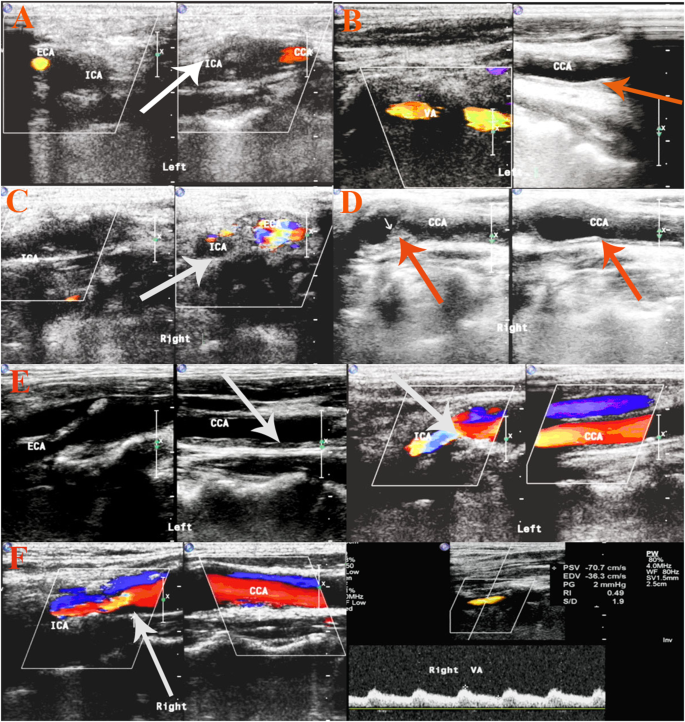

Significant carotid stenosis (≥50%) was identified in 45 (19.3%) of 233 patients at a median interval of 76 months post RT. A representative carotid ultrasound color duplex scan is displayed in Fig. 1.

Representative carotid color duplex scan of two patients. (A–D) was the carotid ultrasonography of one patient. For common carotid artery (CCA) of the right side (R): intimal-medial thickness (IMT) was 1.4 mm; internal carotid artery(ICA): occlusion; For L-CCA: IMT 1.0–1.4 mm, resistance index (RI) 0.74; ICA: occlusion; R- vertebral artery(VA): D 3.9 mm, RI 0.50; L-VA: D 4.4 mm, RI 0.56; (E,F) is the other. R-CCA: IMT 1.2 mm, RI:0.64; ICA: IMT 1.1 mm, RI: 0.61. external carotid artery (ECA): IMT 1.3 mm, RI 0.67. L-CCA: IMT 2.0 mm, RI 0.8. ICA: IMT 1.3 mm, RI 0.66. R-VA: D 3.4 mm, RI 0.65. L-VA: D 4.0 mm, RI 0.60. Note the carotid artery (stenosis arrowheads).